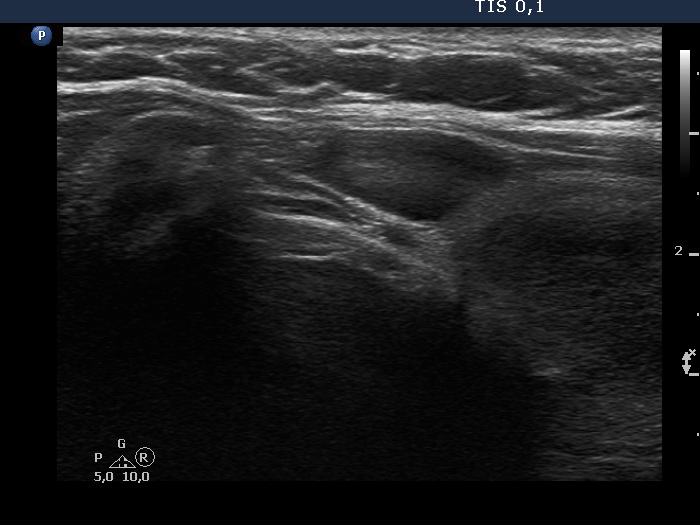

Second examination 3 years later (second, fourth and sixth rows of images):

Ultrasonography. Compared with the previous examination, both the number and the size of discrete lesions in the thyroid have increased.